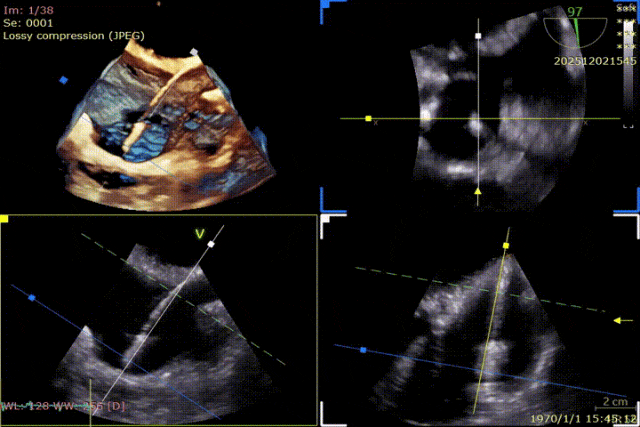

During the procedure, close collaboration was maintained with Dr. Yang Yan (anesthesiologist, Department of Anesthesiology) and Dr. Niu Ming (echocardiography specialist, team of Director Zhai Hong, Department of Cardiac Ultrasound). Guided by transesophageal echocardiography and assisted by DSA imaging, the tricuspid annular structure and regurgitation jet direction were precisely assessed. Ultimately, two 12T K-Clip® devices were successfully implanted. Immediate postoperative echocardiographic evaluation showed a significant reduction in tricuspid regurgitation from 4+ preoperatively to 1+, with a marked decrease in annular area. The surgical outcome was satisfactory.

Dual-clip strategy:

- First clip: 12T (oriented toward the postero-septal commissure, approximately at 5 o'clock)

- Second clip: 12T (oriented toward the antero-posterior commissure, approximately at 8 o'clock)

Advancement of the delivery system into the right atrium

Clip positioned toward the posterior annulus, slightly septal side.

Anchor screw advanced into the annulus.

Opening the clip and adjusting the orientation of the clip arms.

Lifting the annulus and closing the clip.

Evaluating the effect.